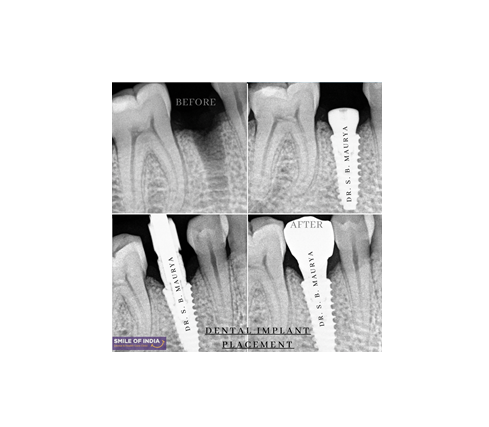

Restoring Function After RCT Failure: A Case of Dental Implant Rehabilitation

The Patient was facing an issue with lower premolar teeth, upon examining we found that the tooth was previously treated (RCT). Now since the tooth has got re-infection and less crown structure left, we decided to replace the tooth with a much more predictable treatment option called dental implant.

There was a fracture of the roots of the lower premolar teeth

The teeth were previously RCT treated.

There were signs of infections beneath the tooth.

Evaluation: We examined the mouth, took X-rays, 3D scans, and impressions.